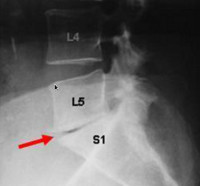

fusion complète

Fusion intervertébrale complète

Coupe Scanner de profil

Votre chirurgien doit assurer votre suivi et vous convoquera en consultation régulièrement jusqu’à qu’il soit sûr de la consolidation complète, puis une surveillance annuelle sous sera proposée.

Il faut savoir que la durée de consolidation est variable d'une personne à l'autre. La consolidation est souvent presque complète après 6 mois.

L'os va continuer à se remodeler jusqu'à environ un an après l'intervention.

L'amélioration des douleurs est nette après l'intervention mais va se poursuivre pendant toute la durée de la consolidation osseuse.